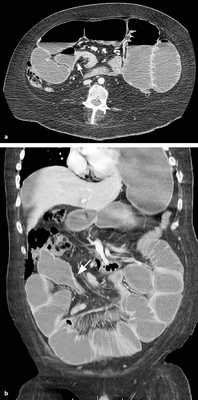

Мальротация кишечника (нонротация) у мужчины 39 лет.

(а, б) Тощая кишка — прямое продолжение двенадцатиперстной (стрелка, а), отсутствуют нормальные 3-й и 4-й сегменты двенадцатиперстной кишки, а также двенадцатиперстно-тощекишечный переход (звездочка, б).

(в, г) Петли тонкой кишки (прямые стрелки) лежат в левой половине брюшной полости, а ободочная кишка (изогнутые стрелки) — в правой половине. Заворот средней кишки у мальчика 11 лет.

Врожденная мальротация кишечника обусловлена нарушением нормальной ротации первичной кишки в направлении против часовой стрелки. Среди широкого разнообразия вариантов мальротации в клинической практике наиболее часто встречают полное отсутствие ротации (нонротация). При этом состоянии тощая кишка служит прямым продолжением двенадцатиперстной, при этом отсутствуют 3-й и 4-й сегменты двенадцатиперстной кишки и двенадцатиперстно-тощекишечный переход. Петли тонкой кишки лежат в левой половине брюшной полости, а ободочная кишка — в правой половине. При завороте средней кишки ножка брыжейки сужена, а двенадцатиперстно-тощекишечный переход (местонахождение связки Трейтца) чаще расположен низко, по правую сторону от средней линии. Такие условия приводят к перекручиванию неправильно фиксированной тонкой кишки, а верхние брыжеечные артерия и вена располагаются в короткой и суженной ножке брыжейки.